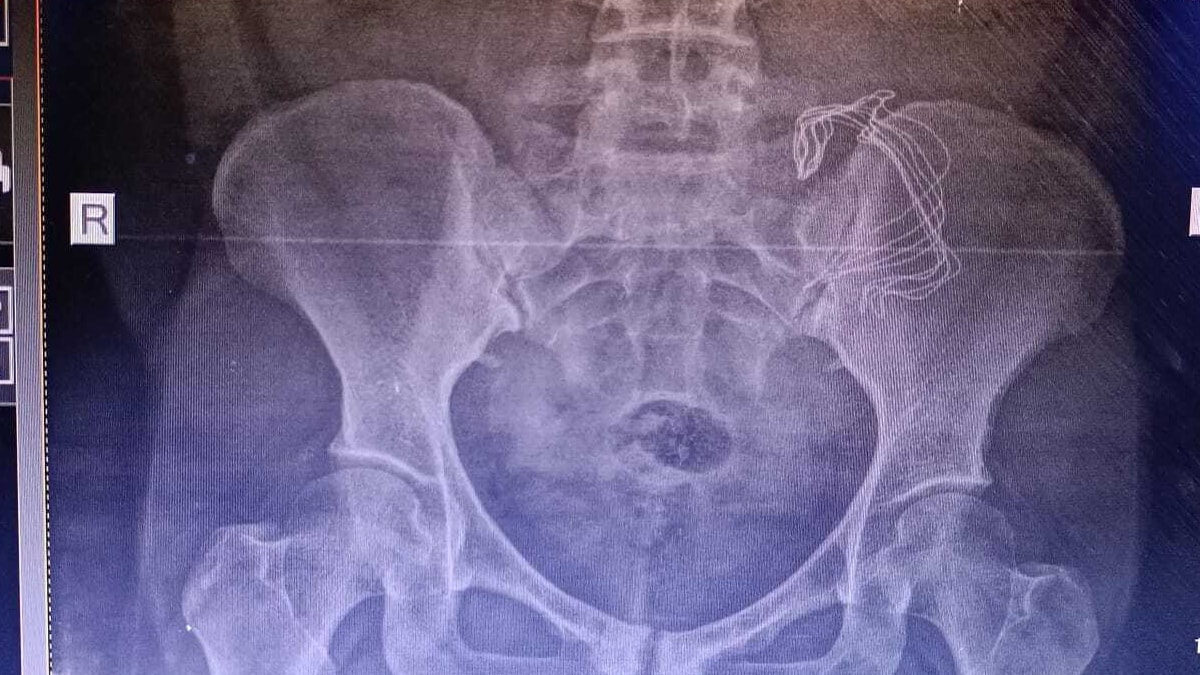

Ağrıları artarak devam eden Ergashova,  geçtiğimiz  Mayıs ayında farklı bir hastaneye başvurdu. Şikayetlerini doktora anlatan Ergashova’dan tomografi çektirilmesi istendi. Tomografiye bakan doktor, Ergashova’nın karnın sol tarafında yabancı bir cisim olduğunu fark etti. Sonuçlardan sonra Ergashova’nın karnındaki cisim 10 ay sonra ameliyat ile alındı.

Hastanede yapılan kontrollerde ve  çekilen tomografide sonra Frangiz Ergashova ameliyata alındı. Ameliyattan sonra Ergashova’nın karnında doğum sonrası unutulan 15 santimetre büyüklüğünde gazlı bez olduğu ortaya çıktı.  Frangiz Ergashova, 10 aydır yaşadığı ağrılara ihmalin neden olduğunu öğrendi. Umut Can ismini verdikleri oğlunun doğumdan sonra 12 gün boyunca küvezde kaldığını söyleyen aile, durumunun şu an iyi olduğunu belirterek hastaneden ve doktordan şikayetçi oldu.

Ameliyatta sargı bezi gibi bir şey çıktı ve iltihaplanmış. 15 cm sargı bezi var dediler. Sargı beziyle gezmişim, İçimde iltihaplanmış. İki çocuğum annesiz kalabilirdi. Ölümden döndüm diyebilirim.”